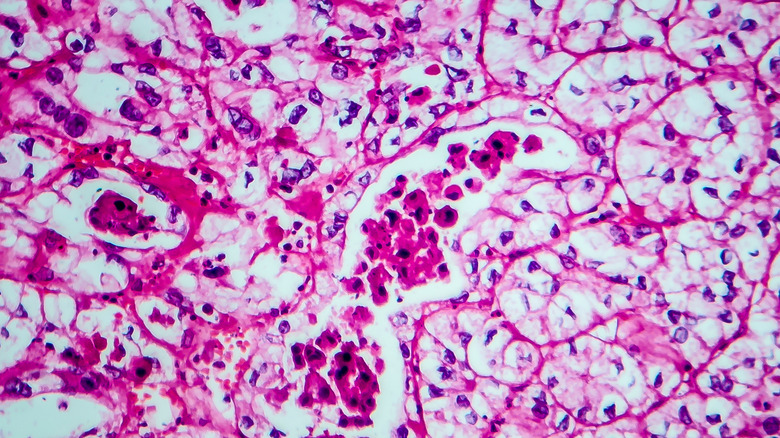

Zooming in on renal cell carcinoma, we can further classify this type of cancer into several sub-types. With the help of a microscope, when you look at the tumor that occurs in people with renal cell carcinoma, you'll see different variations of the cancerous cells. The various appearances provide the basis for the different sub-types (via UCLA Health).

The first sub-type is the clear cell, where three quarters of the cells have a clear or pale appearance. According to Medical News Today, this sub-type causes cancer more than all the other sub-types. The second is the papillary sub-type where cells have extensions that look like fingers. In the third sub-type — chromophobe — the cells can be clear or have a pinkish color with distinguished cell borders. This sub-type has cells bigger than those in the clear cell sub-type. UCLA Health also lists another sub-type that's yet to get named and classified which features tumors that have no characteristics similar to other sub-types.